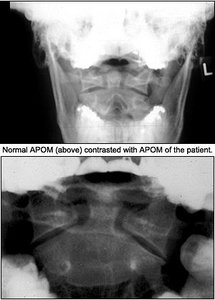

The lateral view isn't very helpful, but the APOM demonstrates a slight depression of the lateral mass of C2 on one side compared to the opposite side. Other than that finding, nothing really appears to be significant. If you didn't have the history, would you have taken the X-rays? If you didn't have the history and the clinical findings, would you have noticed the difference in the lateral masses of C2? It's difficult to say. I'm not certain I would, but the patient had significant discomfort.

This view above evaluates C1-C2, which cannot be visualized clearly on the lateral. The most important element to check is the alignment of the lateral masses of C1. The intervertebral space should be symmetric. The dens can also be evaluated for fracture in this view, but occasionally overlying shadows may give the false impression of a dens fracture (Mach effect). Correlate the findings with the lateral view of the cervical spine. The incidence of fractures to the axis is about 6 percent, and over 50 percent of those fractures involve some part of the dens.